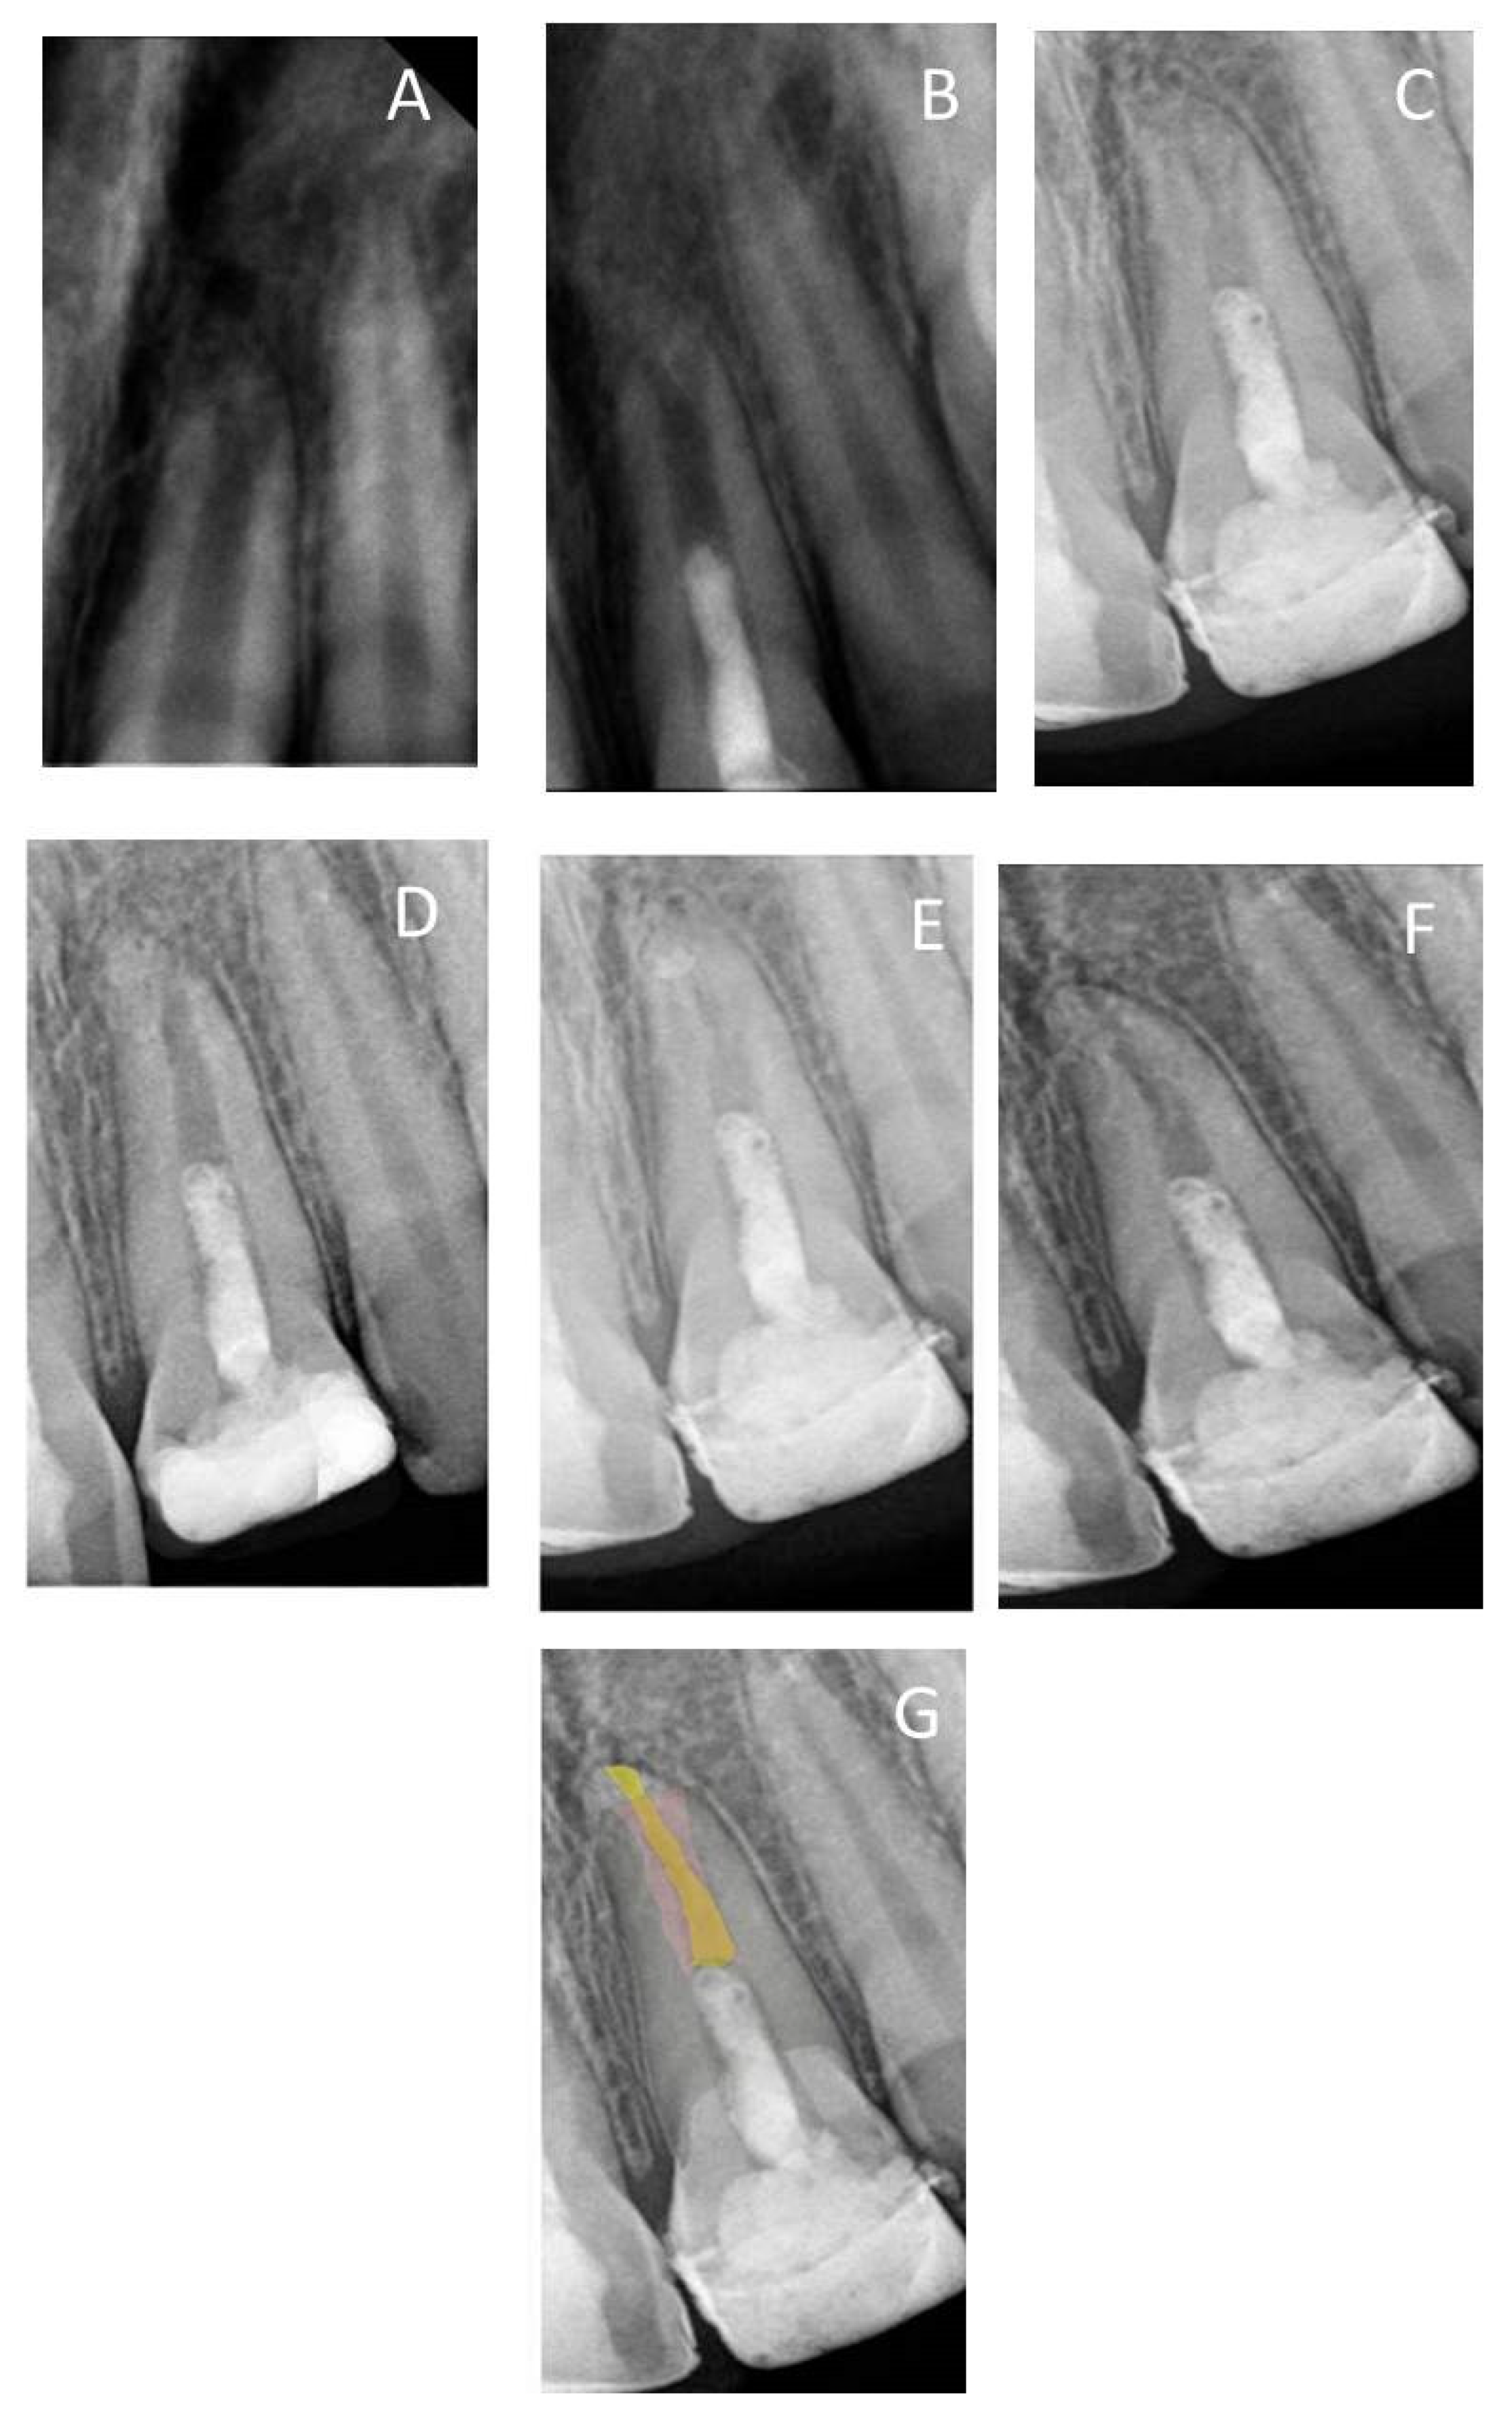

| Follow-Up Time | Median at Each Follow-Up Time (mm) | ||

|---|---|---|---|

| Root Length | Apical Canal Width | Dentin Wall Thickness | |

| Preoperative | 10.36 | 1.14 | 0.48 |

| 6th Month | 10.47 | 1.15 | 0.72 |

| 12th Month | 10.64 | 1.28 | 0.74 |

| 2nd Year | 10.79 | 1.29 | 0.76 |

| 3rd Year | 10.92 | 0.65 | 0.86 |

| 8th Year | 11.4 | 0.24 | 0.98 |